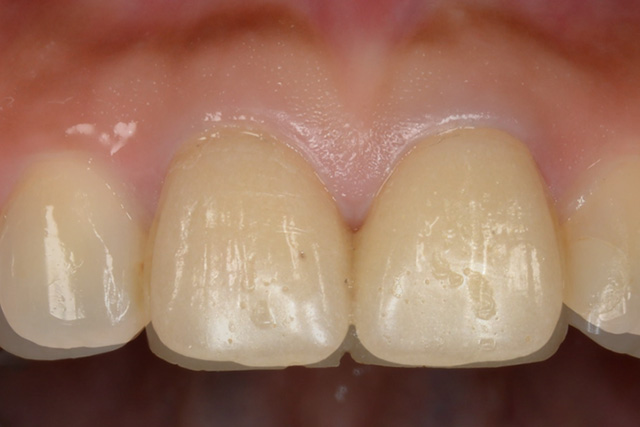

審美症例